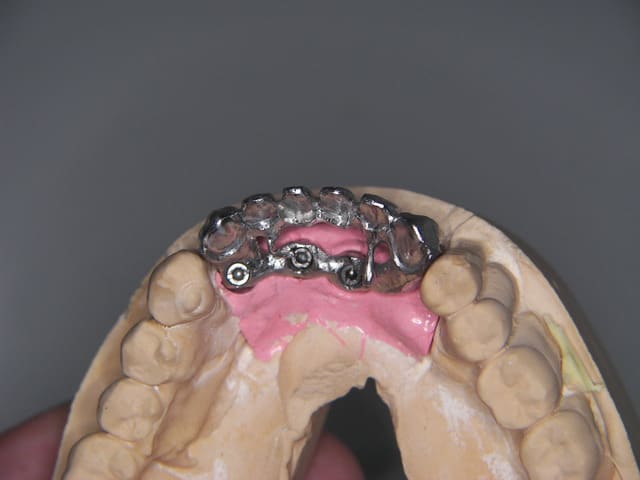

exemple esayage brut de coulé, rectif, preparation armature

le fait de "tout" voir m'aide à réaliser des "trucs" bizarres

C'est IC + couronne (assez peu intéressant...)